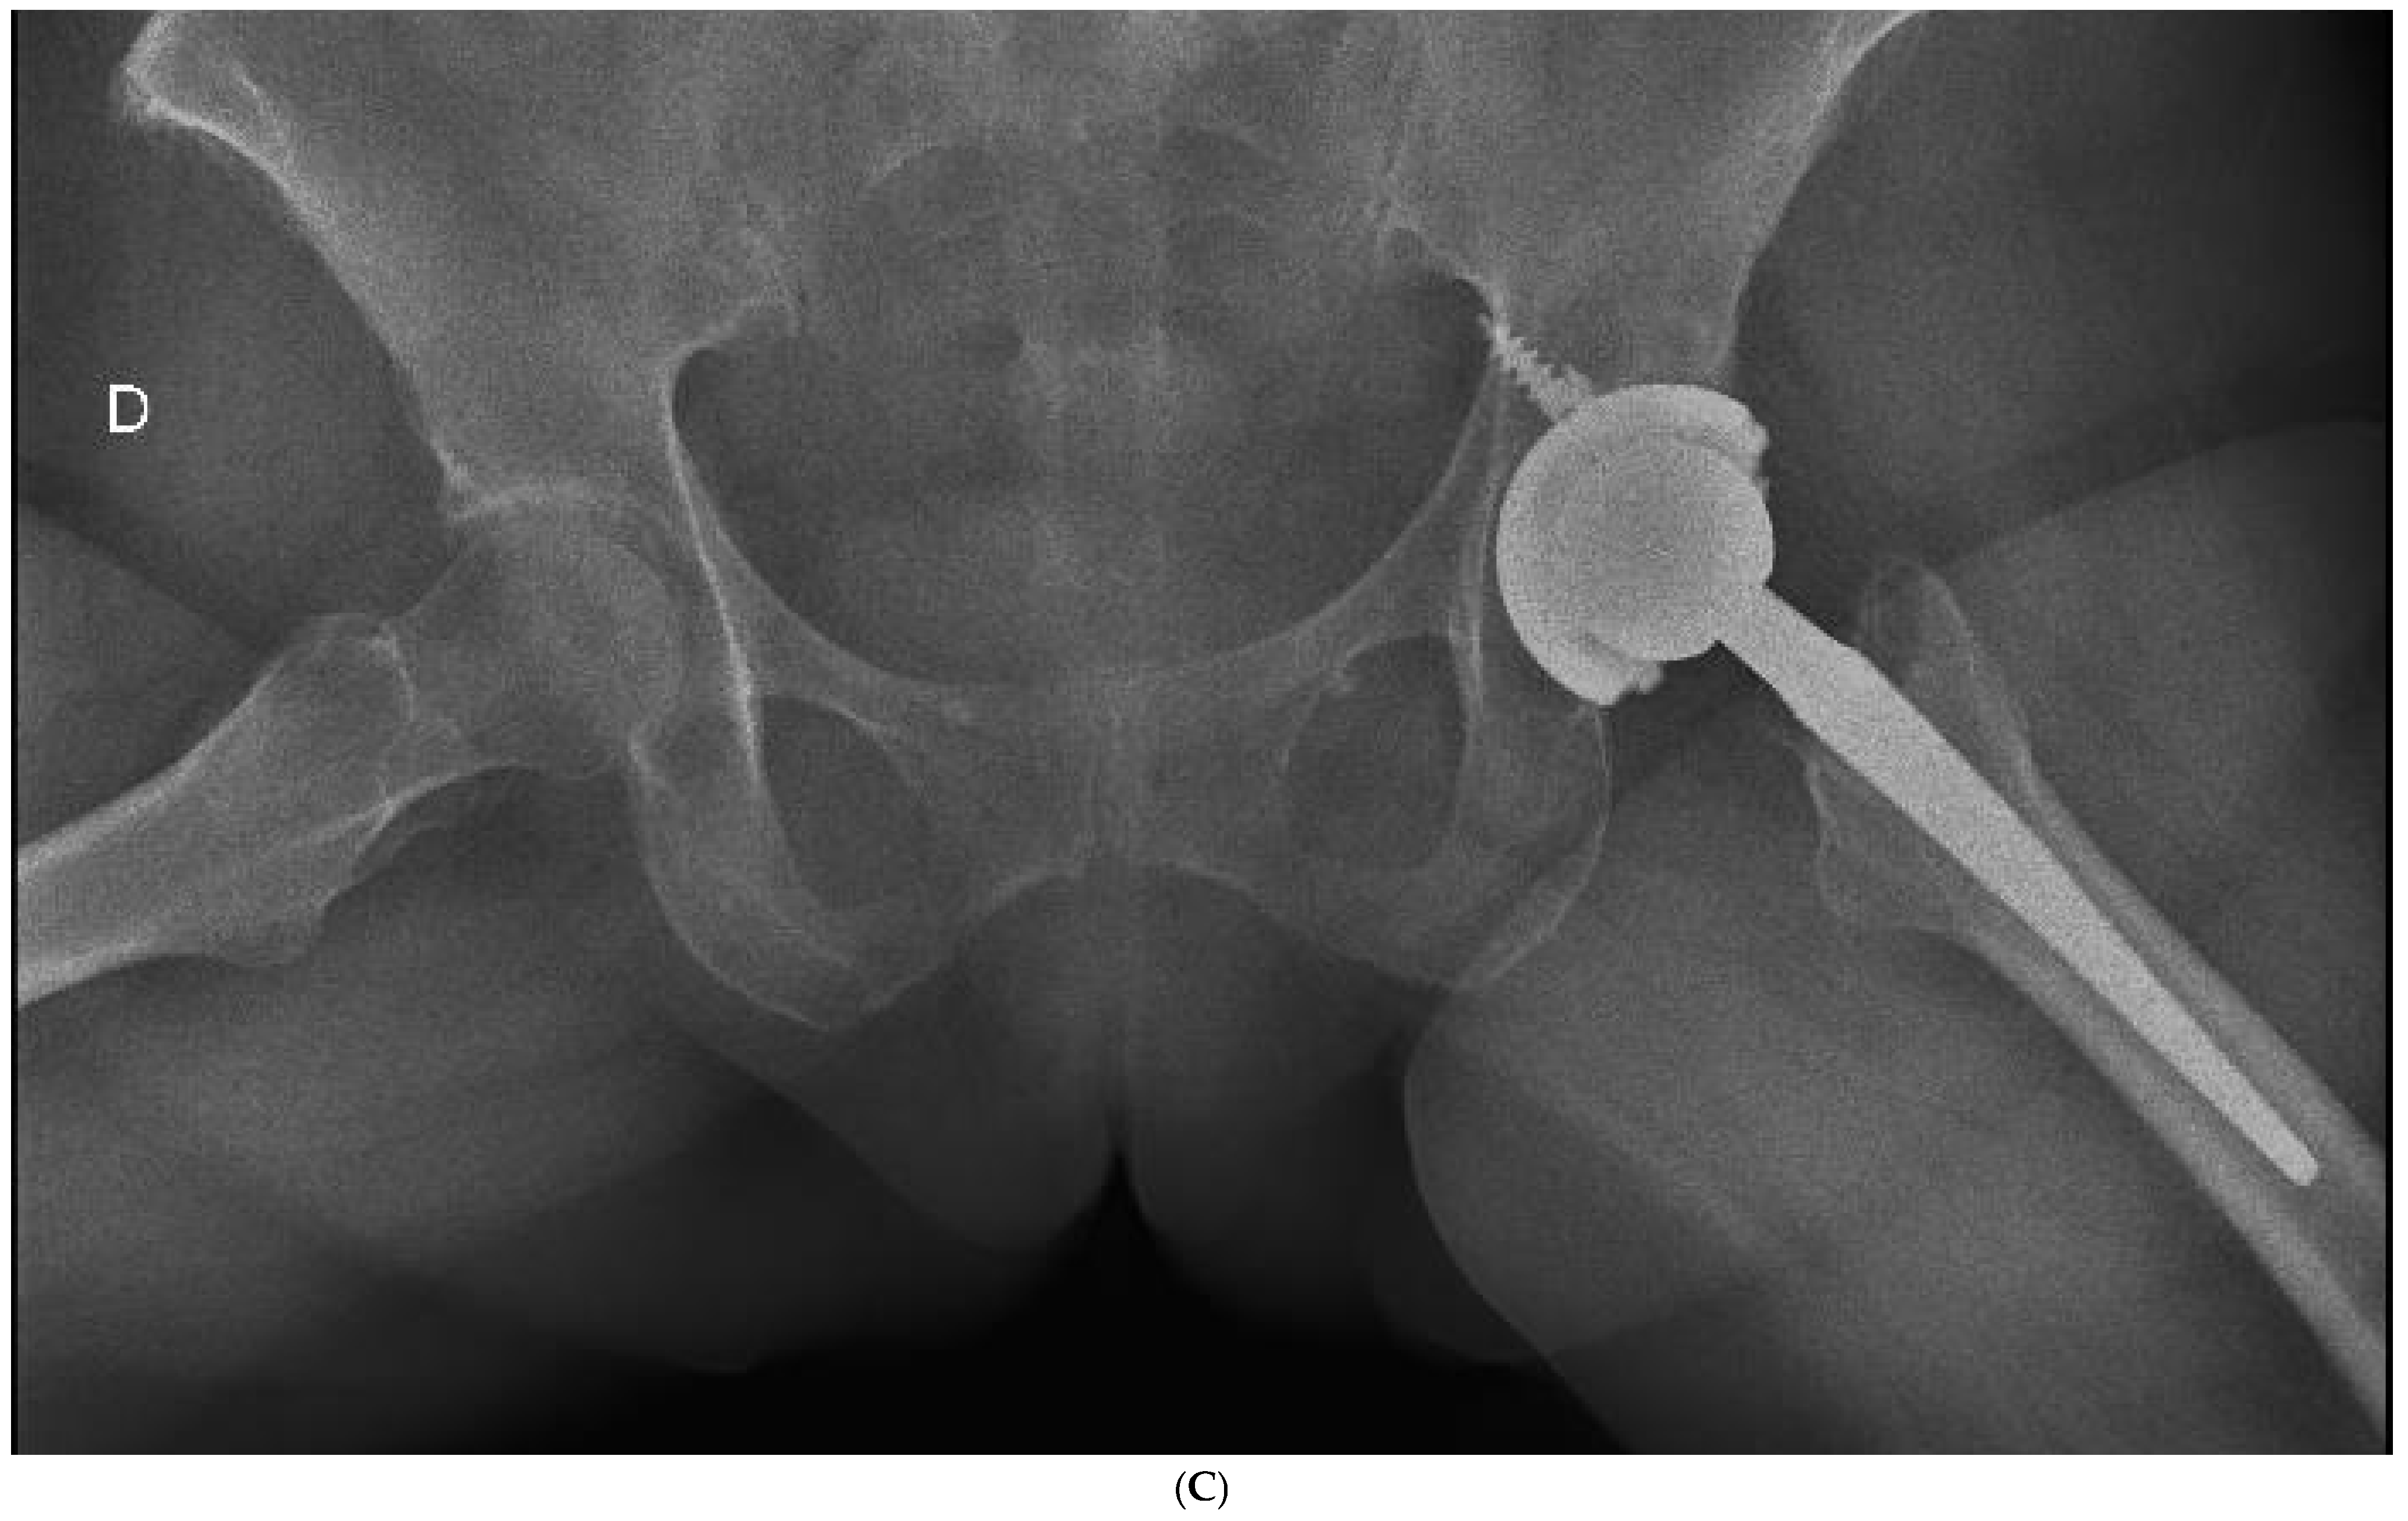

Figure 4.

(A) Preoperative anteroposterior X-ray. Left hip sustained a displaced femoral neck fracture. (B) Postoperative anteroposterior X-ray (CSS group). Femoral stem shows osseointegration and good proximal loading, with no bone resorption at final follow-up. (C) Postoperative lateral X-ray (CSS group). At final follow-up, the stem shows no subsidence and good fixation.